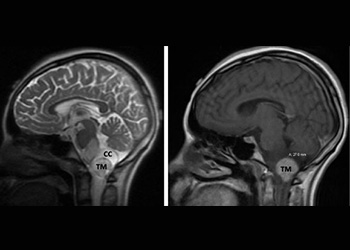

Endovascular:

Hydrocephalus and Brainstem Tumor

Author: Jonathan L. Brisman M.D., F.A.C.S., Read More!

Brain:

74 Year Old Woman with Occipital Headaches

Author: Michael Brisman M.D., F.A.C.S., Read More!